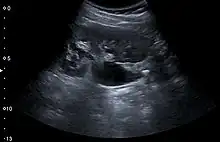

Renal ultrasonography can sometimes be useful, because it gives details about the presence of hydronephrosis, suggesting that the stone is blocking the outflow of urine.[58] Radiolucent stones, which do not appear on KUB, may show up on ultrasound imaging studies. Other advantages of renal ultrasonography include its low cost and absence of radiation exposure. Ultrasound imaging is useful for detecting stones in situations where X-rays or CT scans are discouraged, such as in children or pregnant women.[66] Despite these advantages, renal ultrasonography in 2009 was not considered a substitute for noncontrast helical CT scan in the initial diagnostic evaluation of urolithiasis.[65] The main reason for this is that, compared with CT, renal ultrasonography more often fails to detect small stones (especially ureteral stones) and other serious disorders that could be causing the symptoms.[14]

On the contrary, a 2014 study suggested that ultrasonography should be used as the initial diagnostic imaging test, with further imaging studies be performed at the discretion of the physician on the basis of clinical judgment, and using ultrasonography rather than CT as an initial diagnostic test results in less radiation exposure and equally good outcome.[67]